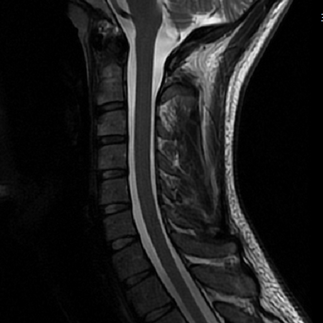

Today's techniques, like MRI (Magnetic Resonance Imaging) and CT (Computed Tomography) scans, offer detailed images of soft tissues and organs. For instance, MRIs can reveal subtle changes in brain structure, while CT scans provide intricate details of internal organs. These advancements have increased diagnostic accuracy, allowing healthcare professionals to detect potentially serious conditions early on.

Neurological Disorders

In neurology, timely detection is critical. Here, MRI scans are invaluable for diagnosing conditions like multiple sclerosis and Alzheimer's disease. Early recognition can lead to effective treatment plans that help manage symptoms and improve patients’ quality of life. For instance, studies indicate that early diagnosis of Alzheimer's can delay symptom progression by up to 3 years with the right interventions.